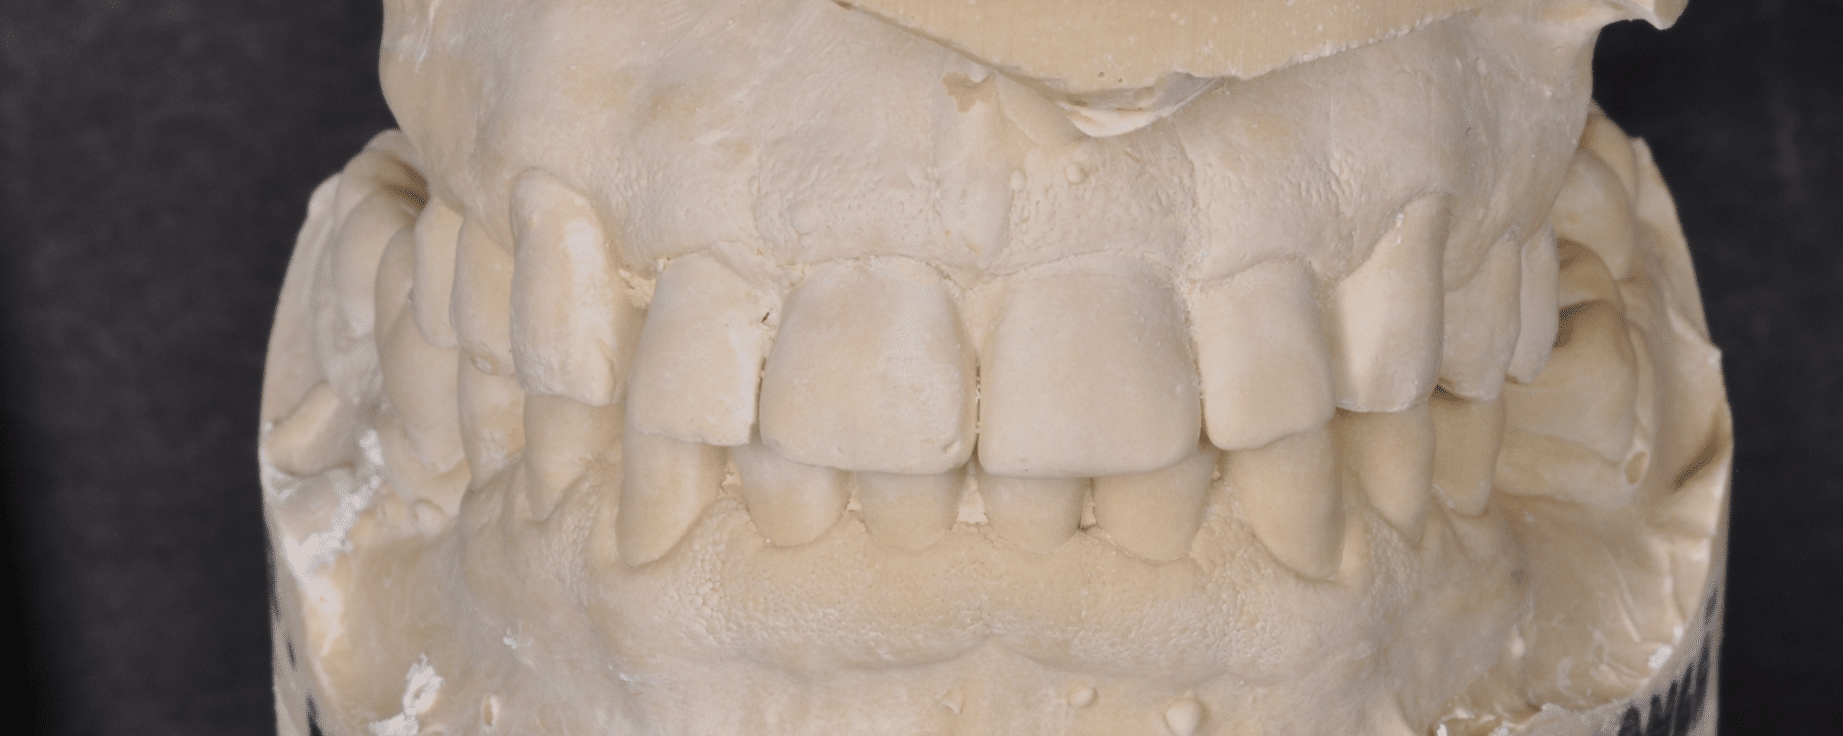

Împreună cu pacientul, am optat pentru inserarea implantelor cu ajutorul ghidului chirurgical pentru a plasa implantul în poziția protetică ideală și pentru a permite realizarea coroanelor insurubate pe implant. A fost efectuată scanarea digitală a arcadelor și a ocluziei pacientului, iar împreună cu tehnicianul radiolog de la DigiRay a fost suprapus fișierul .stl al amprentei digitale peste fișierul .dcm de la CBCT, utilizând software-ul 3Shape.